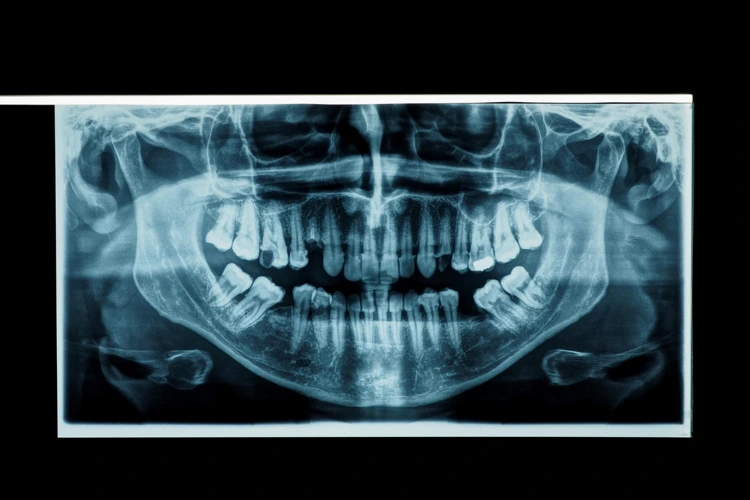

X-Ray

Digital dental radiography is a process that helps produce images of your mouth, just like a regular X-ray. In addition, it scans your mouth almost instantly and stores the digital images on a computer.

The process uses sensors connected to a computer to generate clearer gray-scale images. It makes it easier for the dentist to monitor, detect, diagnose, and treat oral diseases and conditions.

Unlike traditional X-rays that requires film to produce the image, digital dental radiography uses digital X-ray sensors to create enhanced images. It combines electronic sensors and bursts of radiation that pass through soft tissue but are reflected by bones, making them visible. There are three main methods of achieving this:

• Direct: records images through a digital sensor placed in the mouth.

• Indirect: a scanner surveys traditional dental X-rays and converts them into digital format.

• Semi-indirect: combines both digital sensor and scanner to convert an X-ray into digital images.